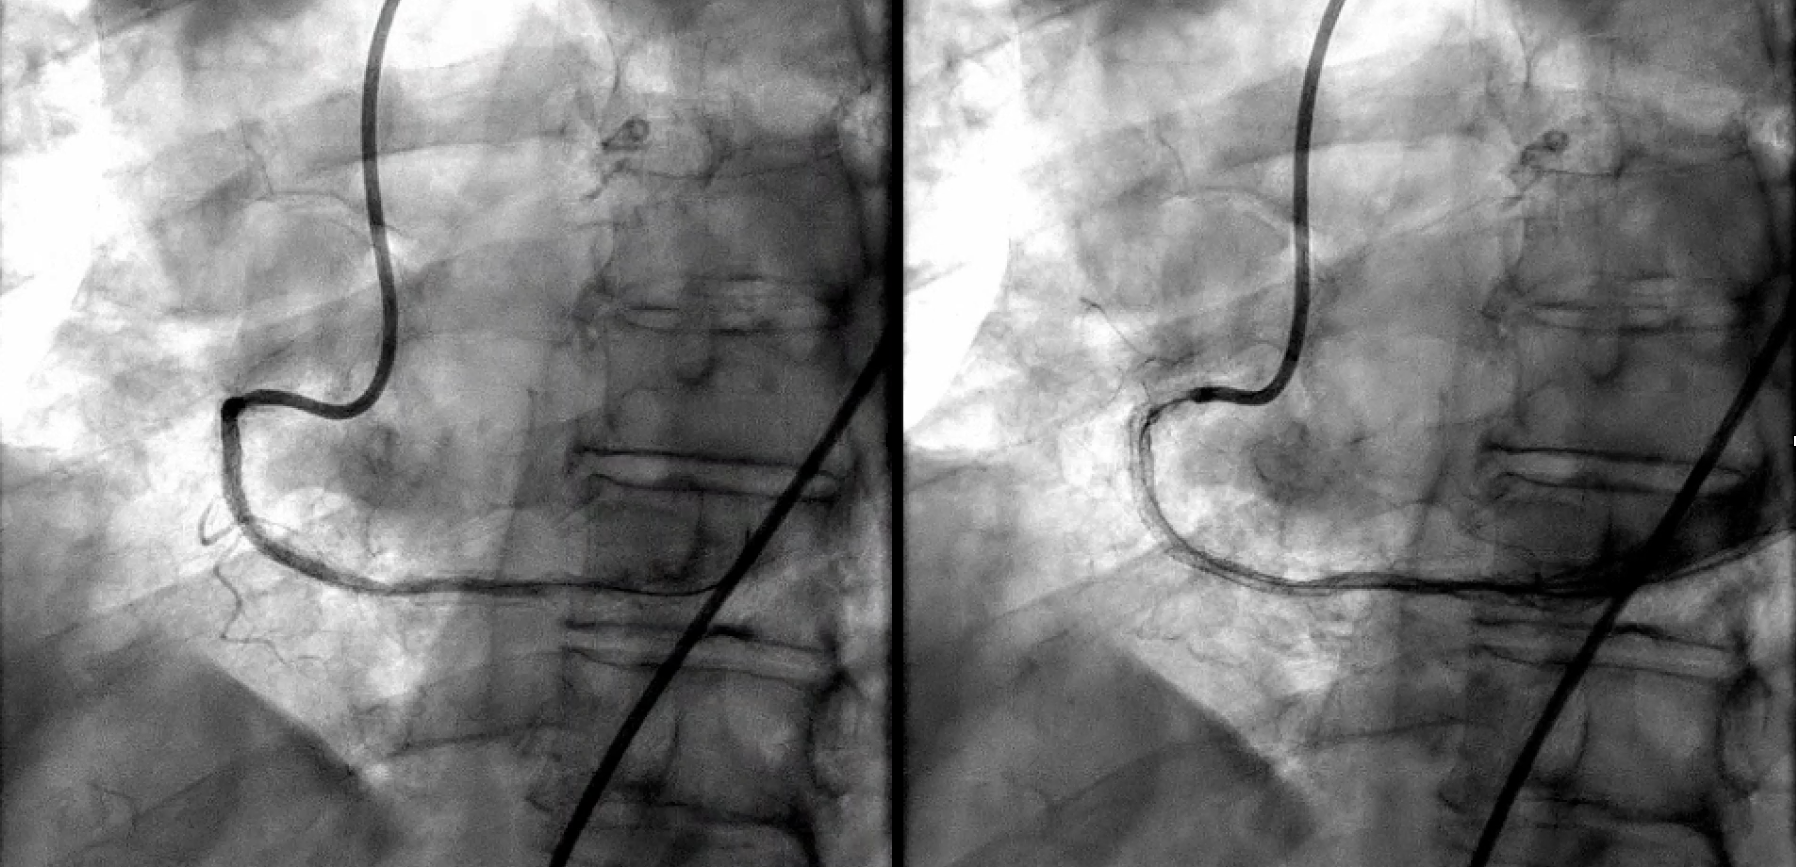

During the CTO procedure, the interventional cardiologist enters the patient’s arteries through a vessel near the groin or wrist. We use catheters (small tubes), wires, and other minimally invasive techniques to approach the CTO blockage. Standard PCI (angioplasty) involves passing the wire through a blockage and performing angioplasty using small balloons and stents. With CTO blockages, specialty wires and catheters are required in order to penetrate the CTO blockage which can be very calcified. Once the wires and devices have crossed the blockage, standard PCI techniques are used to inflate a balloon and open the blockage using stents. This normalizes blood flow.

CTO intervention is more involved and complex than standard PCI, but the procedure is still minimally invasive. In fact, patients often go home the next day and in some cases, the same day. After the procedure, patients’ symptoms tend to improve.

At the start of the procedure, patients receive sedation as in usual heart catheterization procedures. During the procedure, two catheters are placed in arteries (leg or wrist) to allow the ability to go forwards or backwards as needed. Following completion of the procedure, which takes approximately 2-4 hours, the catheters are removed.